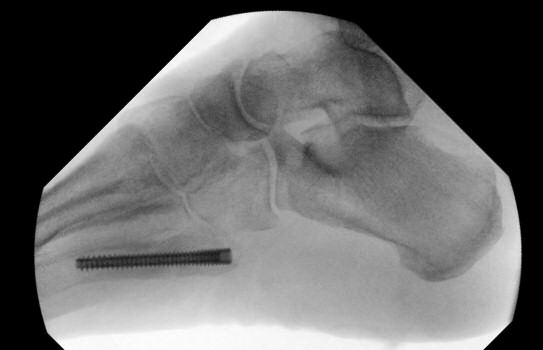

Exempel på Jones-frakturer, första bilden färsk, andra bilden ej läkt, tredje bilden efter operation.